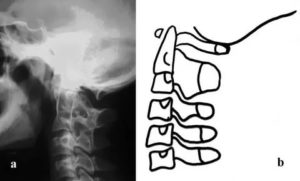

Ассимиляция атланта связана с его частичным или полным сращением с затылочной костью.

Основные опасности, которые несет этот врожденный порок развития, две:

- Сужение большого затылочного отверстия с угрозой сдавливания продолговатого мозга.

- Развитие компенсаторной гиперподвижности в нижнем шейном отделе (как ответ на неподвижность верхнего краниовертебрального отдела).

Симптомы ассимиляции атланта

- Приступообразные головные боли, возможны тошнота и рвота.

- Повышение внутричерепного давления.

- Симптомы ВСД:

- тахикардия, перепады АД, потливость, панические атаки.

При отсутствии компрессии мозга симптомы миелопатии с двигательными нарушениями не выражены.

Возможны диссоциированные (отдельные) расстройства чувствительности в нижней части шейного отдела.

При сдавливании структур продолговатого мозга, симптоматика зависит от уровня компрессии черепно-мозговых нервов: